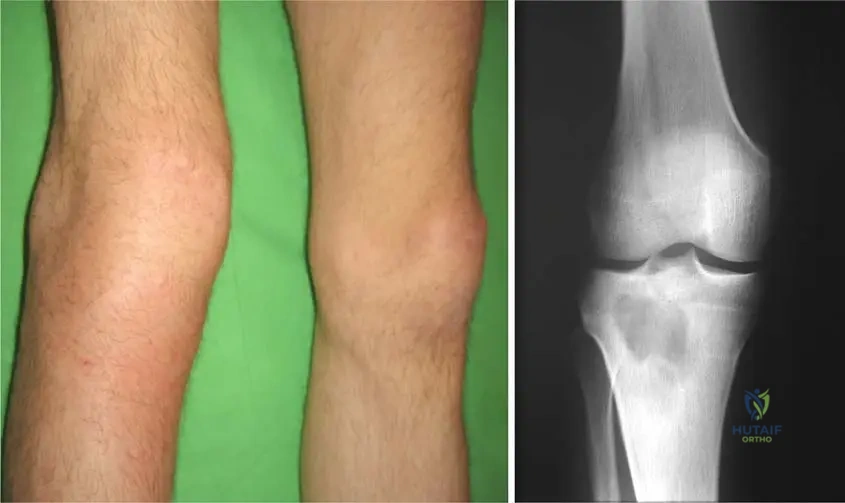

A 10-year-old boy presents with a 1-week history of left proximal tibial pain and limping. Initial radiographs taken 3 days ago were unremarkable. Today, repeat radiographs are performed.

Correct Answer: C

Rationale: Fig. 2.1b specifically illustrates a "well-defined lytic lesion in the proximal metaphysis of the right tibia: no sclerotic margin is observed." This is characteristic of early bone destruction in acute osteomyelitis, which can become visible on radiographs after about 7-10 days. Main Distractor Rationale: A well-defined sclerotic lesion (A) or extensive cortical thickening (D) are typically seen in chronic osteomyelitis or benign bone lesions, not acute presentations.

A 9-year-old boy presents with right knee pain, swelling, and erythema. Radiographs show a well-defined lytic lesion in the proximal metaphysis of the right tibia, notably without a sclerotic margin. This radiographic appearance, as seen in Fig. 2.1b, is most characteristic of which stage or type of osteomyelitis?

Rationale: Fig. 2.1b specifically describes "a well-defined lytic lesion in the proximal metaphysis of the right tibia: no sclerotic margin is observed. Biopsy proved osteomyelitis." This appearance is characteristic of early acute osteomyelitis, where bone destruction is occurring without sufficient time for reactive bone formation (sclerosis) or involucrum. Chronic osteomyelitis (A) typically shows sclerotic margins, sequestrum, and involucrum. Brodie's abscess (B) is a subacute form with a well-defined lytic lesion often with a sclerotic rim. Extensive cortical destruction (D) might be present but the lack of sclerosis is key. Post-traumatic osteomyelitis (E) can be acute or chronic, but the specific radiographic finding points to the acute stage.